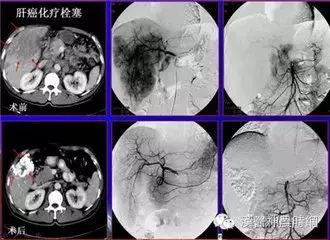

(3)动脉插管化疗 如颈外动脉分枝插管治疗头颈癌,肝动脉插管治疗原发性肝癌或肝转移癌。